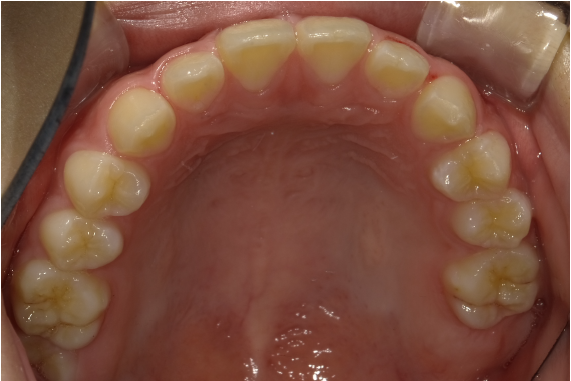

顎顔面矯正は、「急速拡大装置」を利用し、正中口蓋縫合と呼ばれる部分を広げ、顎骨の成長を促していきます。下の画像のように「ねじ」を回すことで装置を徐々に広げていきます。

顎顔面矯正は一般的な矯正と異なり「顎を拡大」するのですが、特に「上の顎」を拡大することが大きな特徴です。これを行うことで、先ほどのメリットが副次的効果として生まれます。